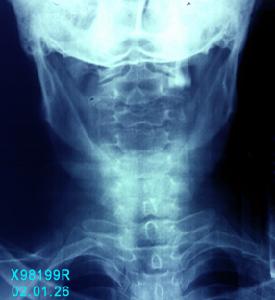

頸椎伴上肢放射痛,頸後伸時加重,受壓神經根皮膚節段分布區感覺減弱,腱反射減弱,肌萎縮,活動受限。X線顯示:椎體增生,鉤椎關節增生明顯,椎間隙變窄,椎間孔變小。